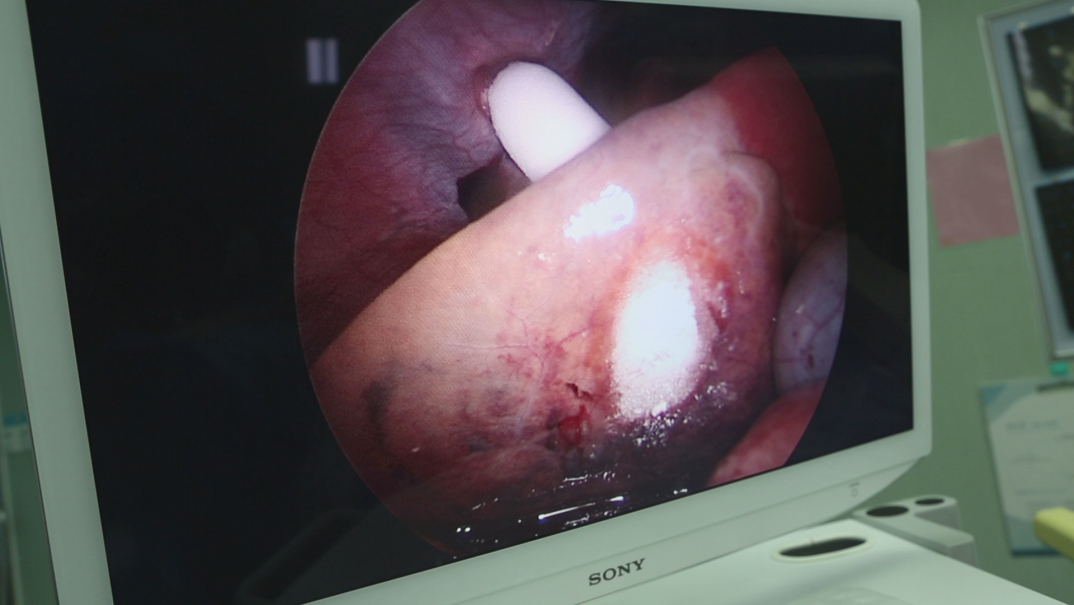

2020年5月11日,懷著忐忑心情的阿萊平臥在手術(shù)臺上,心情五味雜陳。在麻藥的作用下她靜靜的沉睡在夢中。因為肝臟周圍布滿大血管,需要經(jīng)驗豐富的醫(yī)生才能根據(jù)影像巧妙避開血供豐富的血管和重要的神經(jīng)。主刀醫(yī)師牛立志院長先通過DSA精準定位腫瘤部位、大小、數(shù)量、血供等情況,在腹腔鏡下準確的找到腹腔動脈、肝動脈、腸系膜上動脈選擇性插管,再熟練的拿起冷凍針將腫瘤冷凍成球,不傷至大血管及重要的器官,只留下1~2mm傷口,同時腹腔鏡輔助隔離技術(shù)可以有效隔離結(jié)腸和膽囊,保護重要的組織,從而達到根治性消融腫瘤目的。手術(shù)花費近2個小時才順利結(jié)束。

拍攝于2020.5.11